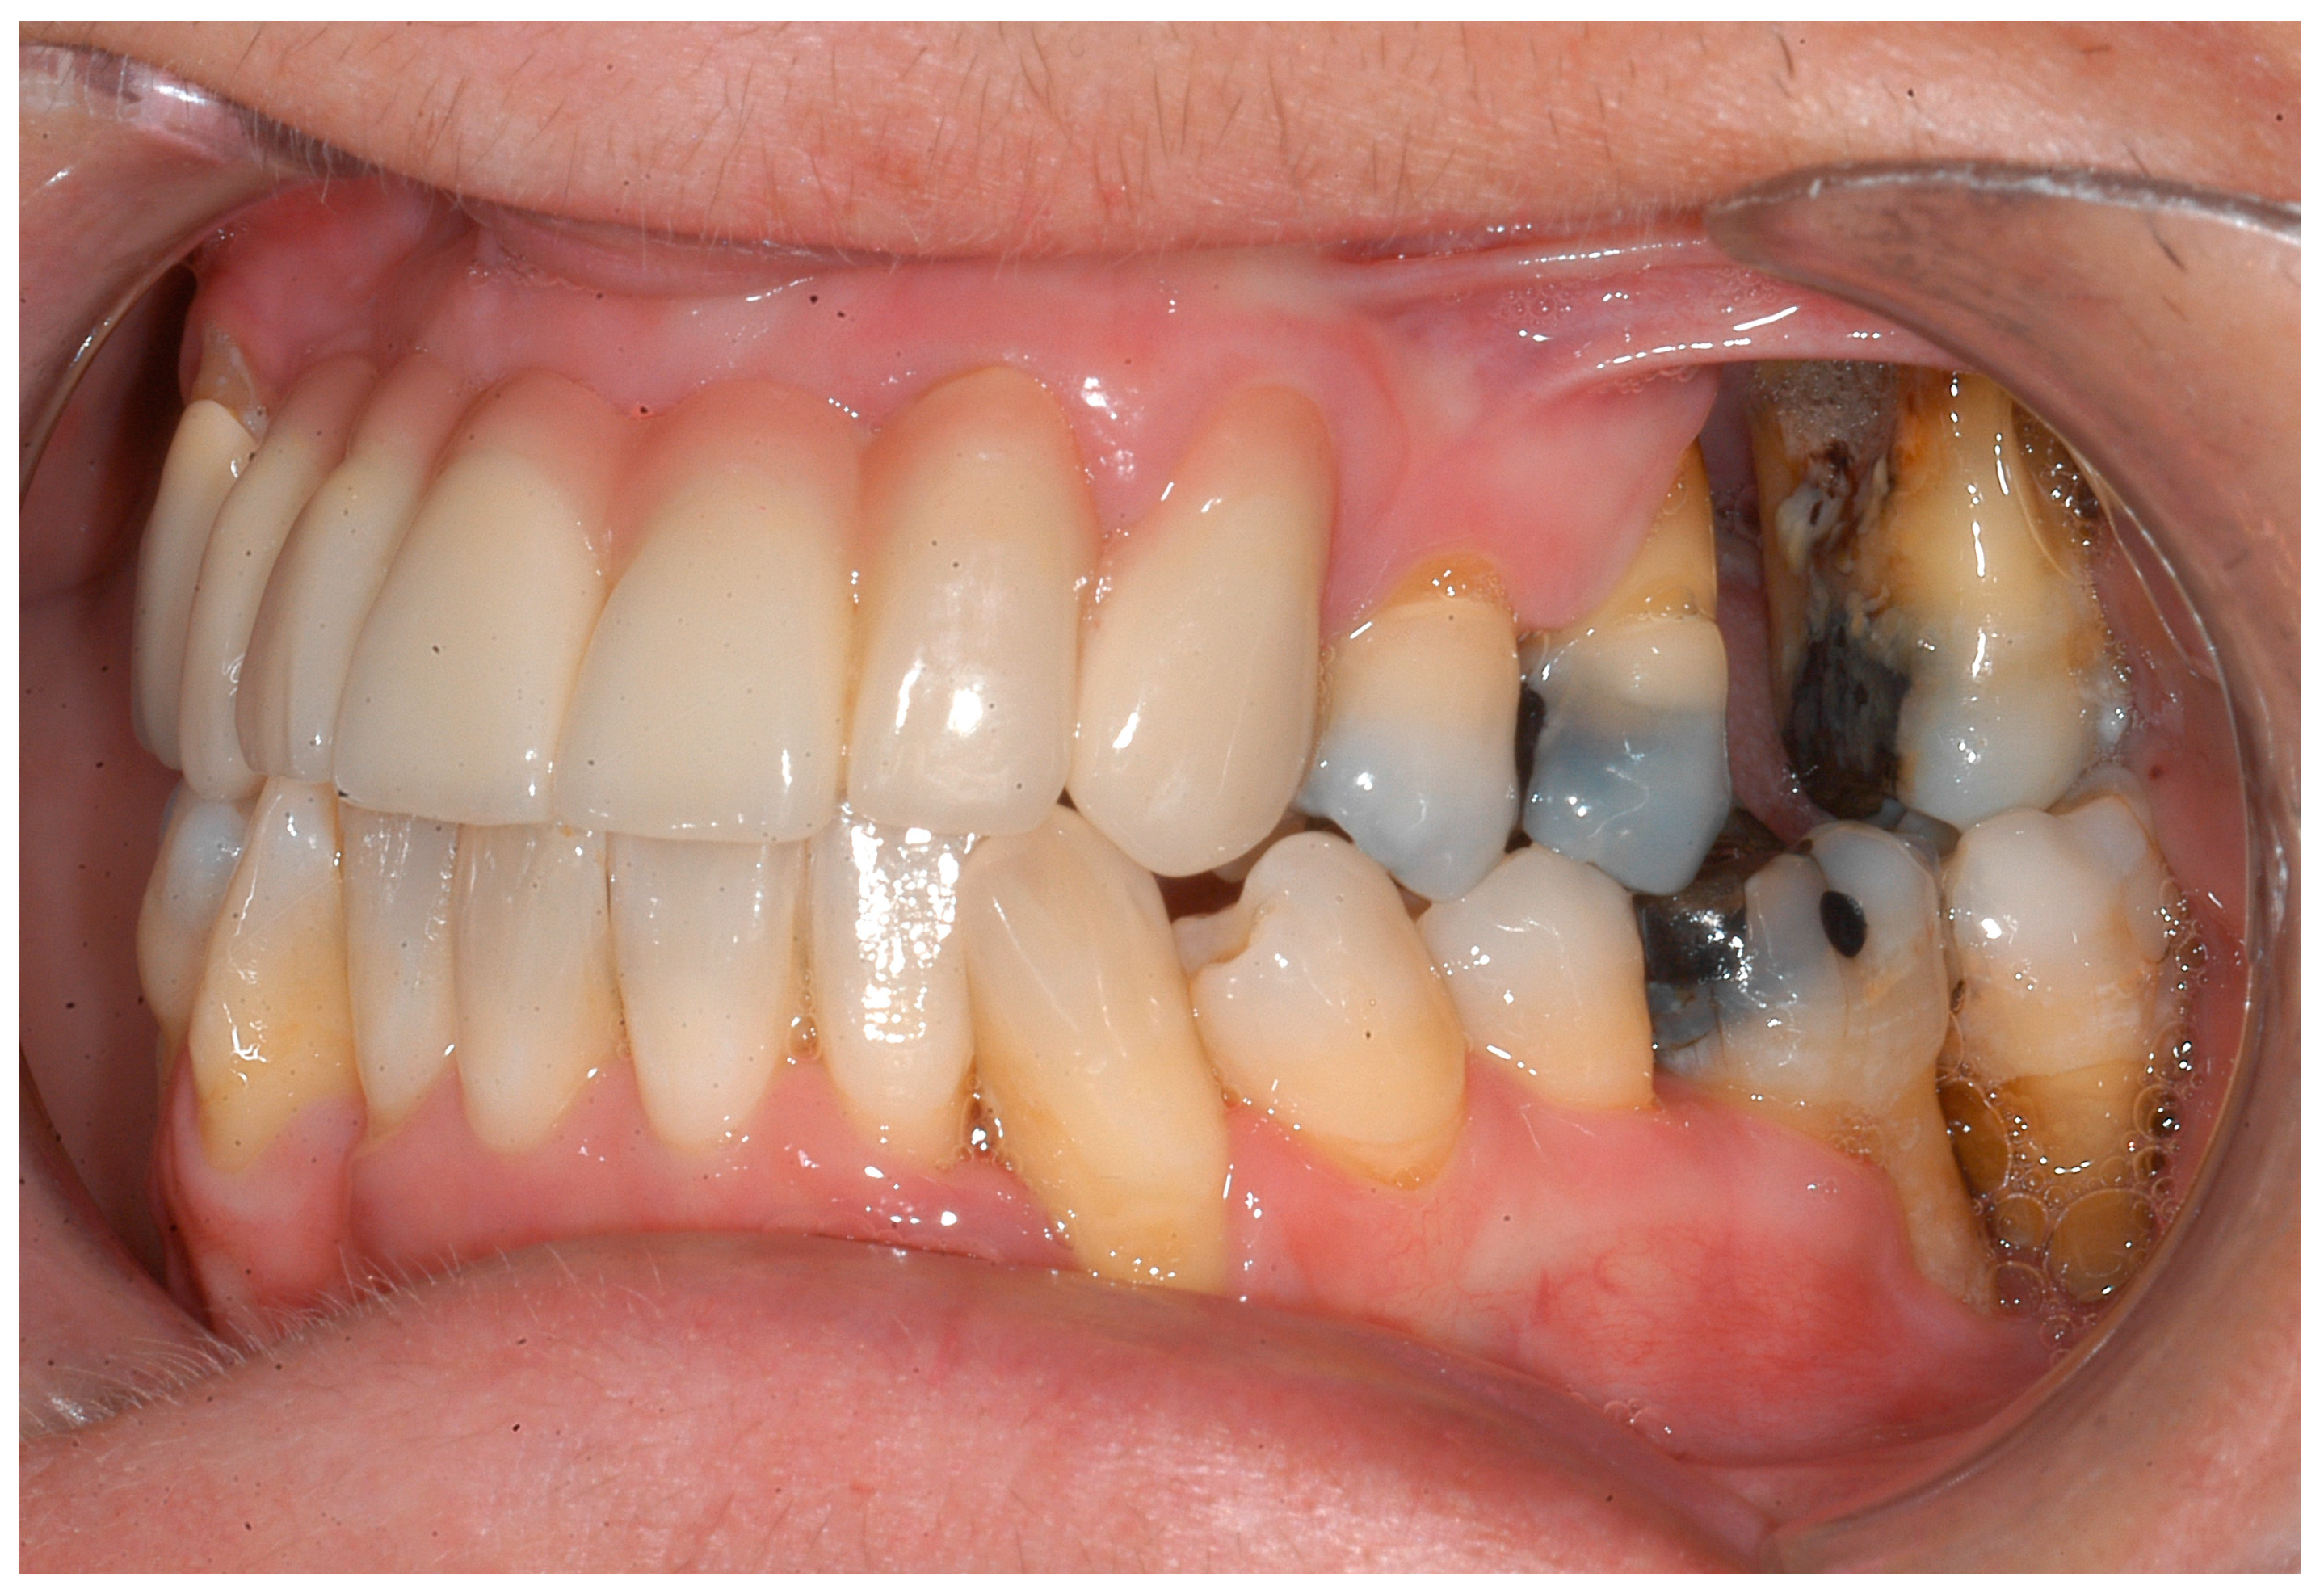

- Hanisch, M.; Jung, S.; Kleinheinz, J. Identification of rare diseases in the oral cavity. Internist 2018, 59, 972–980. [Google Scholar] [CrossRef] [PubMed]